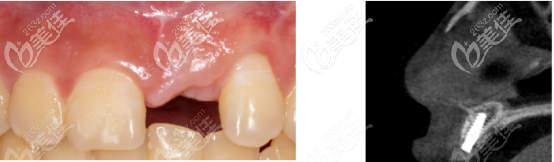

術后半年通過上面CT可以看出,骨量確實沒有發(fā)生吸收:

術后半年cbct照片中,可以看到牙齦愈合良好,而且骨量足夠做二期手術。

先安裝3.6×5mm愈合基臺,三周后進行印模的制取。